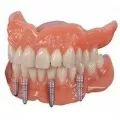

Имплантация — это единственный способ нормализации функциональности челюсти в случае полной утраты зубных единиц. В челюстную кость вкручивают искусственный стержень, который выполняет роль зубного корня. После приживления к нему крепят коронку, по форме и цвету не отличающуюся от натуральной. При наличии сохранившихся корней возможна установка зубной коронки на них. Такой вариант идеален для тех, кто хочет решить проблему надолго.

Имплантация может применяться как при частичной потере зубов, так и при абсолютном их отсутствии.

| Протезирование на имплантах: | |

| АLL-ON-4 | от 100000 руб. |

| ALL-ON-6 | от 200000 руб. |

| Бюгельные протезы на имплантах | 80000-200000 руб. |